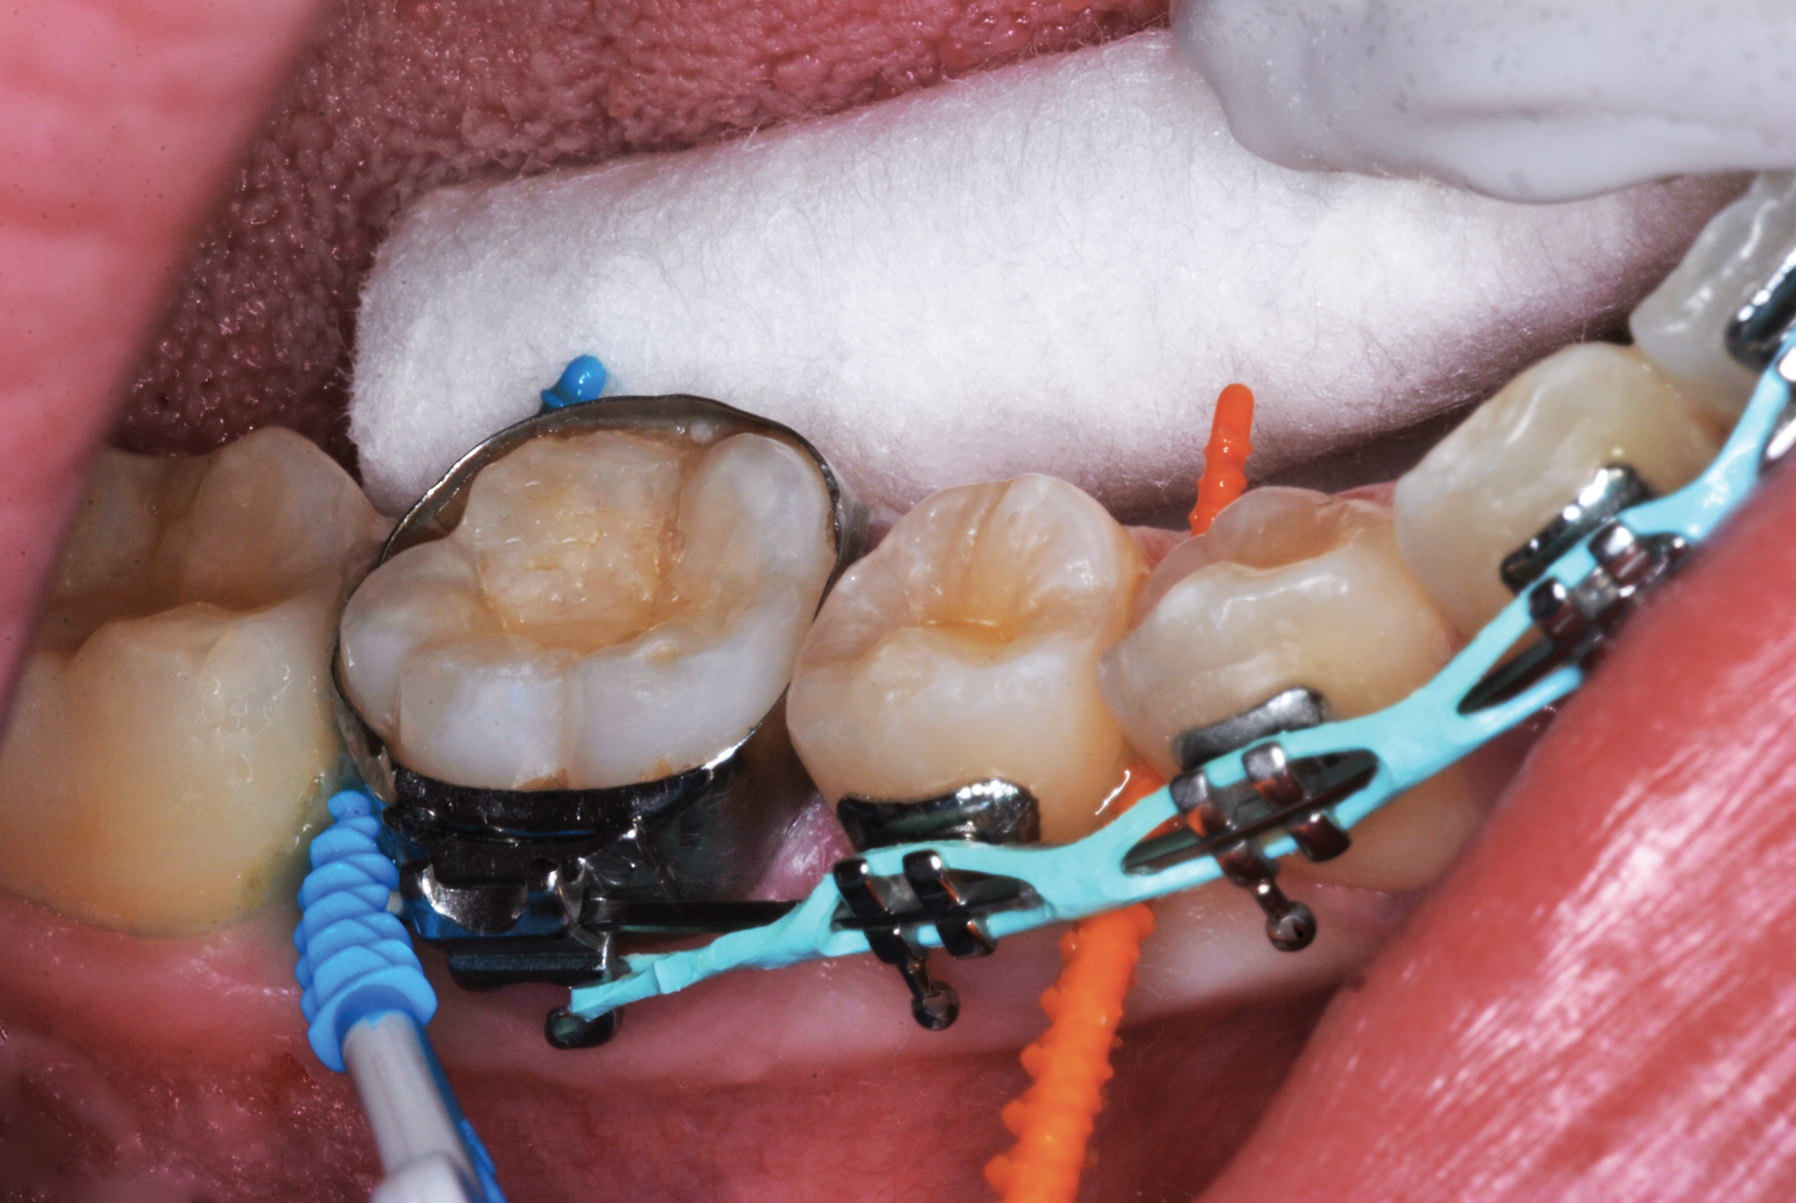

Fig 10. Interproximal sites in orthodontic patients can also benefit from preventive or interceptive SDF applications.

Figure 10